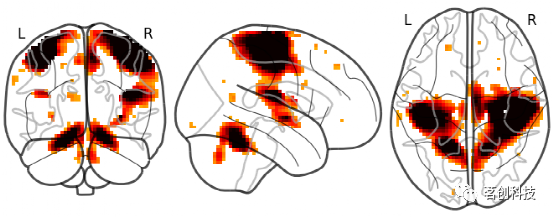

plot_glass_brain:绘制玻璃脑图像。默认情况下,plot_glass_brain使用一种名为'ortho'的显示模式,它会产生三个投影,等价于在plot_glass_brain中指定display_mode='ortho'。

from nilearn import plotting

from nilearn.plotting import plot_glass_brain

# 整个大脑的矢状切面和地图的阈值是3

plot_glass_brain(stat_img, threshold=3)